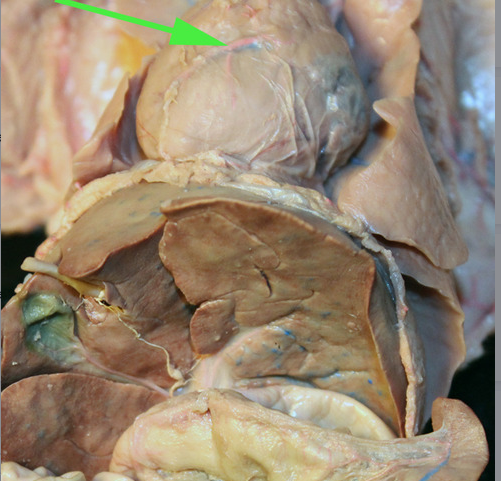

The organ marked by the green arrow is part of the THYMUS gland